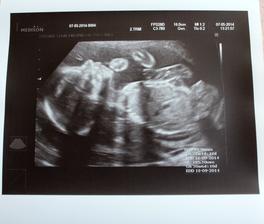

7.5. Velký utz, účastnil se i tatínek a moje mamka... Pan doktor potřetí potvrdil HOLČIČKU a hlavně úplně zdravou, všechno má předpisové, poslechli jsme si průtoky krve, spočítali prstíky :o) Pan doktor poznamenal, že je to pěkná divoška, že snad se vyřádí v děloze, že jinak by ji domů nechtěl :o) Mamka konečně přibrala, váha 57 kg.